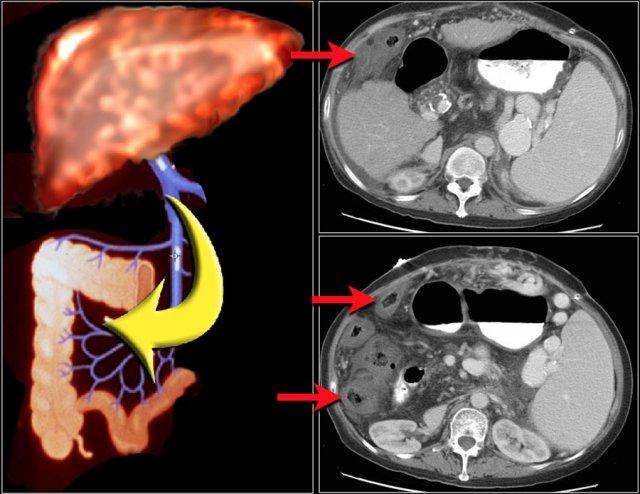

Thiếu máu cục bộ mạc treo ruột

Thiếu máu cục bộ ruột thường ảnh hưởng đến đại tràng và hay gặp nhất ở góc lách, đại tràng xuống và đại tràng sigma.

Nguyên nhân chủ yếu là do tình trạng giảm lưu lượng máu như sốc giảm thể tích hoặc suy tim sung huyết.

Đặc biệt ở người cao tuổi có dày thành ruột, cần luôn đưa thiếu máu cục bộ vào danh sách chẩn đoán phân biệt.

Một nguyên nhân đặc biệt gây thiếu máu cục bộ ruột non là tắc ruột quai kín, sẽ được thảo luận ngay sau đây.

Đây là hình ảnh bệnh nhân thiếu máu cục bộ ruột do huyết khối tĩnh mạch mạc treo tràng trên – SMV (mũi tên đỏ).

Lưu ý tình trạng ứ máu tĩnh mạch trong mạc treo ruột (mũi tên vàng).

Đây là một bệnh nhân khác bị thiếu máu cục bộ một đoạn dài ruột non do tắc ruột quai kín.

Một đặc điểm hình ảnh quan trọng của tắc ruột quai kín là hình ảnh các quai ruột non giãn xếp theo kiểu nan hoa bánh xe với các mạch máu mạc treo hội tụ về một điểm trung tâm.

Các dấu hiệu thiếu máu cục bộ trong tắc ruột quai kín tương tự như ở các bệnh nhân có nguyên nhân thiếu máu cục bộ mạc treo khác:

- Dày thành ruột

- Phù nề mạc treo ruột

- Cổ trướng

- Sự ngấm thuốc của thành ruột trong thiếu máu cục bộ có thể bình thường, tăng do hiện tượng tái tưới máu, hoặc giảm/mất ngấm thuốc như trong trường hợp này.